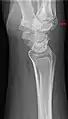

Additional images